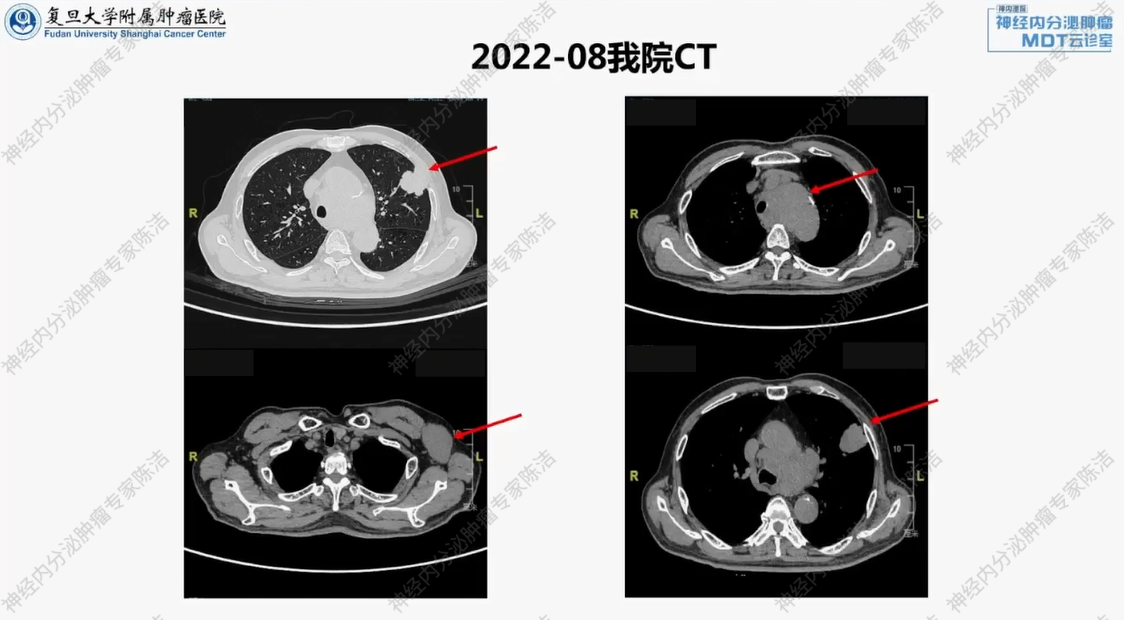

我院诊疗经过:因“发现左侧腋窝肿块”于2022年8月就诊。

胸部CT示:左侧腋下、左肺上叶胸膜下存在占位性病变,原发灶待排查,纵膈内多发肿大淋巴结,转移待排除。